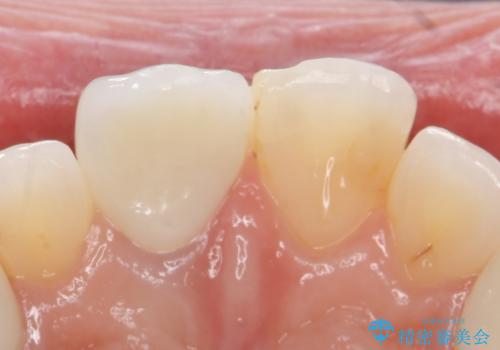

- 右上1の前歯の見た目が気になるので被せ物をやり替えたいといらっしゃった方の症例です。

再根管治療終了後、オールセラミッククラウン(スペシャル)によって隣在歯に合わせた補綴を行いました。